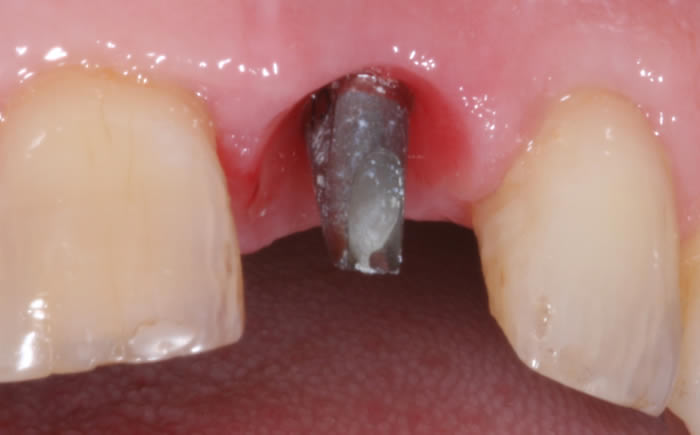

More front teeth replaced by dental implants

Case Three (4 images)